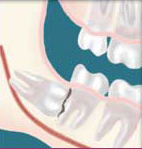

Complete Bony Impactions: There is NO space for the tooth to erupt. It remains totally below the jawbone or if even partially visible requires complex removal techniques.

Unusually Difficult Complete Bony Impactions: The impacted Wisdom tooth is in an unusual and difficult to remove position. This situation can also arise when the shape of the jawbone and other facial structures make removal of this tooth significantly more difficult.

Disease - Non-infectious diseases can also arise in association with an impacted wisdom tooth. Cysts are fluid-filled "balloons" inside the jawbone which are associated with impacted wisdom teeth and slowly expand destroying adjacent jawbone and occasionally teeth. They can be very difficult to treat if your wisdom teeth are not removed in your teenage years. Although rare, tumors can be associated with the delayed removal of wisdom teeth.